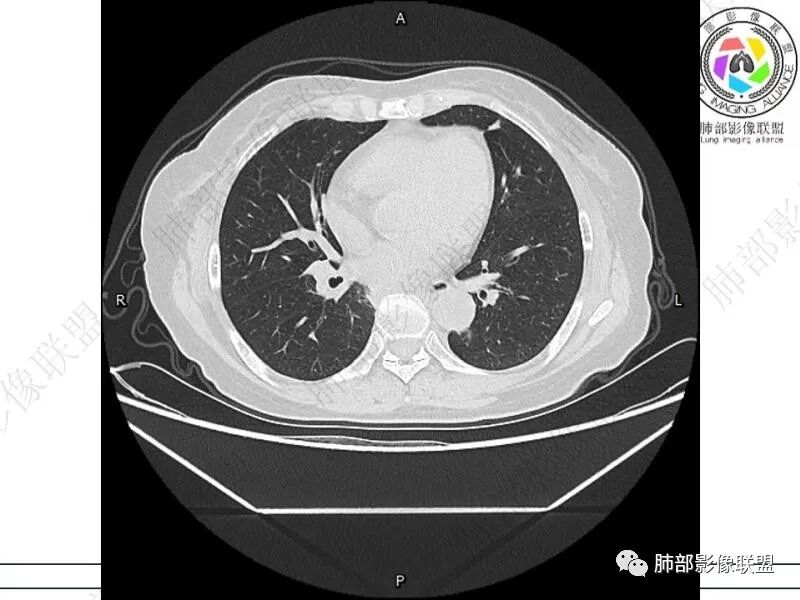

谢加平:结肠癌术后史,两肺胸膜下多发结节及斑块实变病灶,实边边界平直征(亚急性和慢性病变过程),双肺下叶后基底段胸膜下为甚,与胸膜平行特点,见支气管充气征,边缘模糊的GG0,首诊2022年11月18日肺部CT,与治疗11月28日对比,病灶未吸收,双肺下叶胸膜下病灶有侧向融合特点,综合分析符合炎性肉芽肿,隐球菌感染。

老年女性,结肠癌术后。两下肺胸膜下为主片状实变,右下肺短期复查融合且病灶长轴平行于胸膜,实变内可见支气管充气征,边缘磨玻璃晕,另两肺内胸膜下散在数枚小结节状、楔形实性灶。考虑感染性病变,隐球菌可能,鉴别肺转移。

THINKER:胸膜下实变,常见OP丶PC丶PE丶腺癌丶腺病毒丶非典型病原体。1.此例肠癌,免疫妥协人群,PC要考虑,但荚膜抗原阴性,阴性预测值很高。2.肿瘤史,本身易高凝状态,肺栓塞要考虑。3.OP  胸膜下实变,经典型OP影像。故:PE>OP>PC

2.影像特征:双肺胸膜下多发实性结节、磨玻璃影及实变影,胸膜下优势分布、晕征、胸膜下脂肪间隙存在,部分病灶边界平直征,有侧向融合趋势。